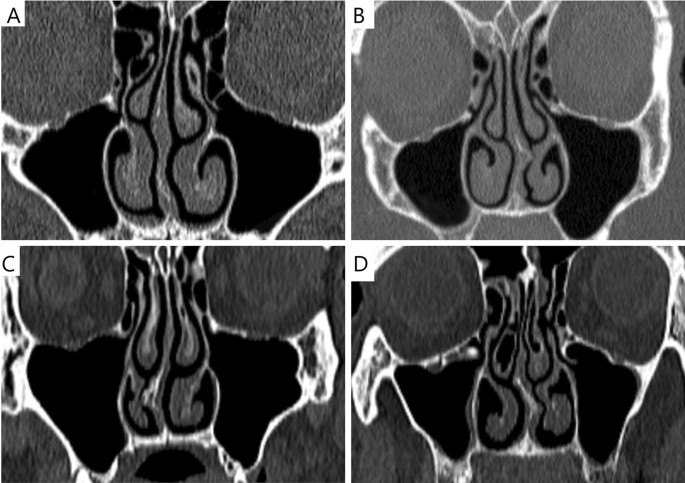

副鼻腔炎は急性と慢性に分かれ、慢性副鼻腔炎ではCTによる含気腔の透過性変化を評価することが診断の鍵になります。

含気骨は慢性的な病変にも関与することがあり、炎症や粘膜肥厚の継続は構造の変形や機能障害につながります。特に、慢性副鼻腔炎やアレルギー性鼻炎との関係が深く、生活の質を大きく左右する疾患となります。

慢性疾患との関係性は以下の通りです。

- 慢性副鼻腔炎

↳長期間にわたる粘膜炎症で含気腔の形態が変化しやすい - 鼻茸(ポリープ)形成

CT・MRI画像での含気骨の見方

含気骨は空洞(含気腔)を持つ構造のため、画像上では“黒く抜ける”部分として認められ、骨・粘膜・液体の変化によって明らかに異なる所見を呈します。画像を読む際には以下の点がポイントになります。

まず、基本的な見え方と確認すべきポイントを整理します。

- 含気腔の典型的所見:骨〜空気〜軟組織の陰影変化

↳空気=低吸収(CTでは黒に近い)、骨=高吸収(白に近い) - 左右対称・形状・大きさの確認

↳正常では左右に大きな差がないことが多いが、個人差あり - 異常所見のチェック項目:

・粘膜肥厚/液体貯留(含気腔内に液体やムチンが入ると灰色〜白っぽく写る)

・骨壁の破壊・骨変形(慢性炎症や腫瘍で起こりうる)

・開口部の狭小化・閉塞(鼻腔、副鼻腔道の交通障害)

例えば、乳突蜂巣(側頭骨内の含気腔)を薄層CTで観察すると、含気化の程度が術前リスクの指標になるという報告があります。 また、上顎洞(上顎骨にある含気腔)では、慢性副鼻腔炎の際、粘膜肥厚・液体貯留・骨肥厚がCT上明らかになります。 こうした所見を系統的にチェックできるよう、画像を読む習慣をつけることが重要です。